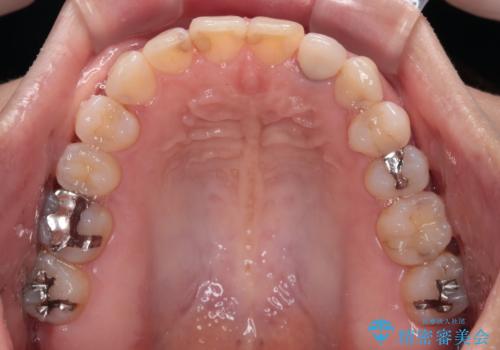

開咬と変色した前歯 インビザライン矯正とオールセラミッククラウン治療

- 前歯の開咬と失活により変色した前歯を気にして来院された患者様です。

開咬の治療は、前歯を閉じるように引っ張り出すよりも、上下臼歯を圧下(骨内にめり込ませる)させることで進める方が長期的に安定した歯列を維持できます。

インビザラインは臼歯の圧下を効果的に行えるため、インビザラインを用いて矯正治療を行うこととしました。

矯正治療が概ね終了した時点で前歯をオールセラミッククラウンにて補綴治療を行い、その後インビザラインにて細かい部分を仕上げていくことしました。